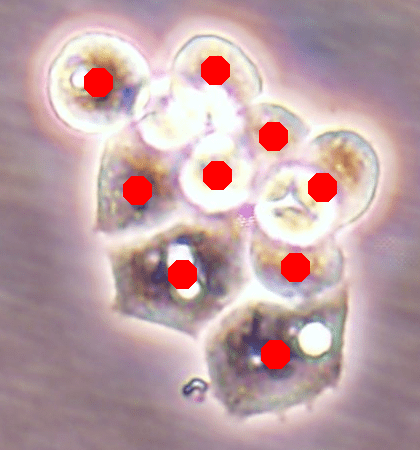

![]() |

| (a) | (b) | (c) | (d) |

Likewise, Fig. 7a shows the maps of calculated outer distances when the ground truths are given. Figs. 7b, 7c, and 7d show the outer distance maps estimated by SingleOuter, DeepDistance, and its extended version, respectively. It is observed that a single-task SingleOuter method is less accurate in estimating outer distances especially for pixels close to cell boundaries. Due to this incorrect estimation, it locates only a single cell for each of the cell pairs shown inside green ellipses, resulting in under-segmentations for these cell pairs. Our multi-task DeepDistance models yield better estimations for these boundary pixels. However, it is important to note that our models do not use the estimated outer distances in a detection algorithm but define this estimation as an auxiliary task. Particularly, this distance is defined to represent a different aspect of the problem and its estimation is considered as complementary to the main task. Concurrent learning of two related tasks with a multi-task model, which uses shared feature representations, better helps avoid local optima. In other words, when two related tasks share the same representations (with a shared encoder path), it is more difficult to finetune these representations for only one of these tasks. This is effective to obtain better learning performances for individual tasks, as also shown in Figs. 6 and 7.